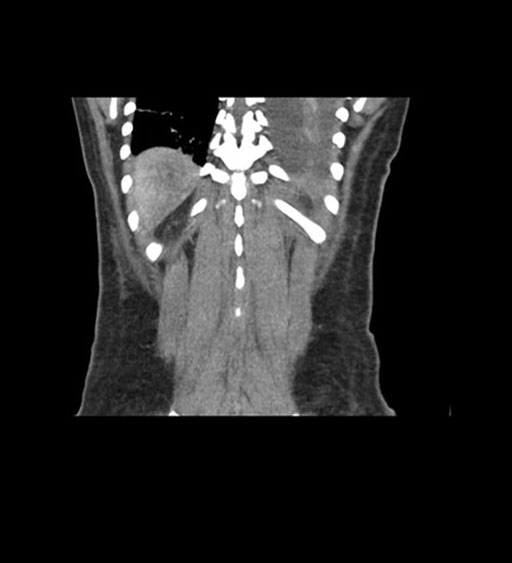

Coronal Arterial

Imaging analysis

Based on initial findings, which issue(s) would you be most concerned about?